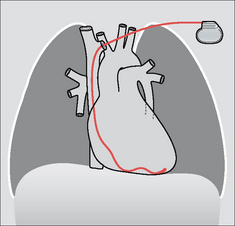

image

Figure 12.5 Optimal electrode positions. Dual chamber pacemaker. Pacemakers tend to be introduced from the left side in right-handed patients.